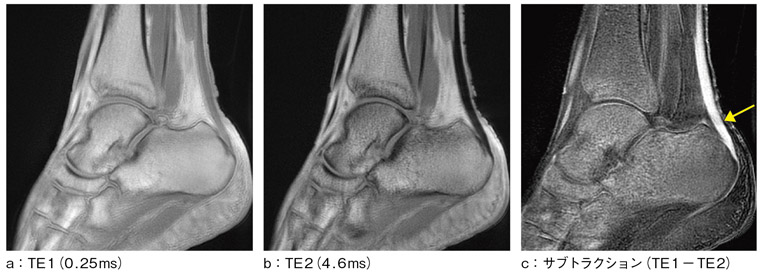

●μTEの信号補正技術

μTEによるボランティア画像例を示す。図5は,アキレス腱の画像例である。主なシーケンスパラメータはFOV 150mm,スライス厚5mm,スキャン時間 6:44である。図5 aはファーストエコーの画像で,TEは0.25msの超短TEによる画像である。全体的に高信号となった画像が得られている。図5 bはセカンドエコーの画像で,TEは4.6msである。図5 cはファーストエコーからセカンドエコーを画像差分したものであり,T2の短いアキレス腱が明瞭に描出されている。

図5 アキレス腱撮像例